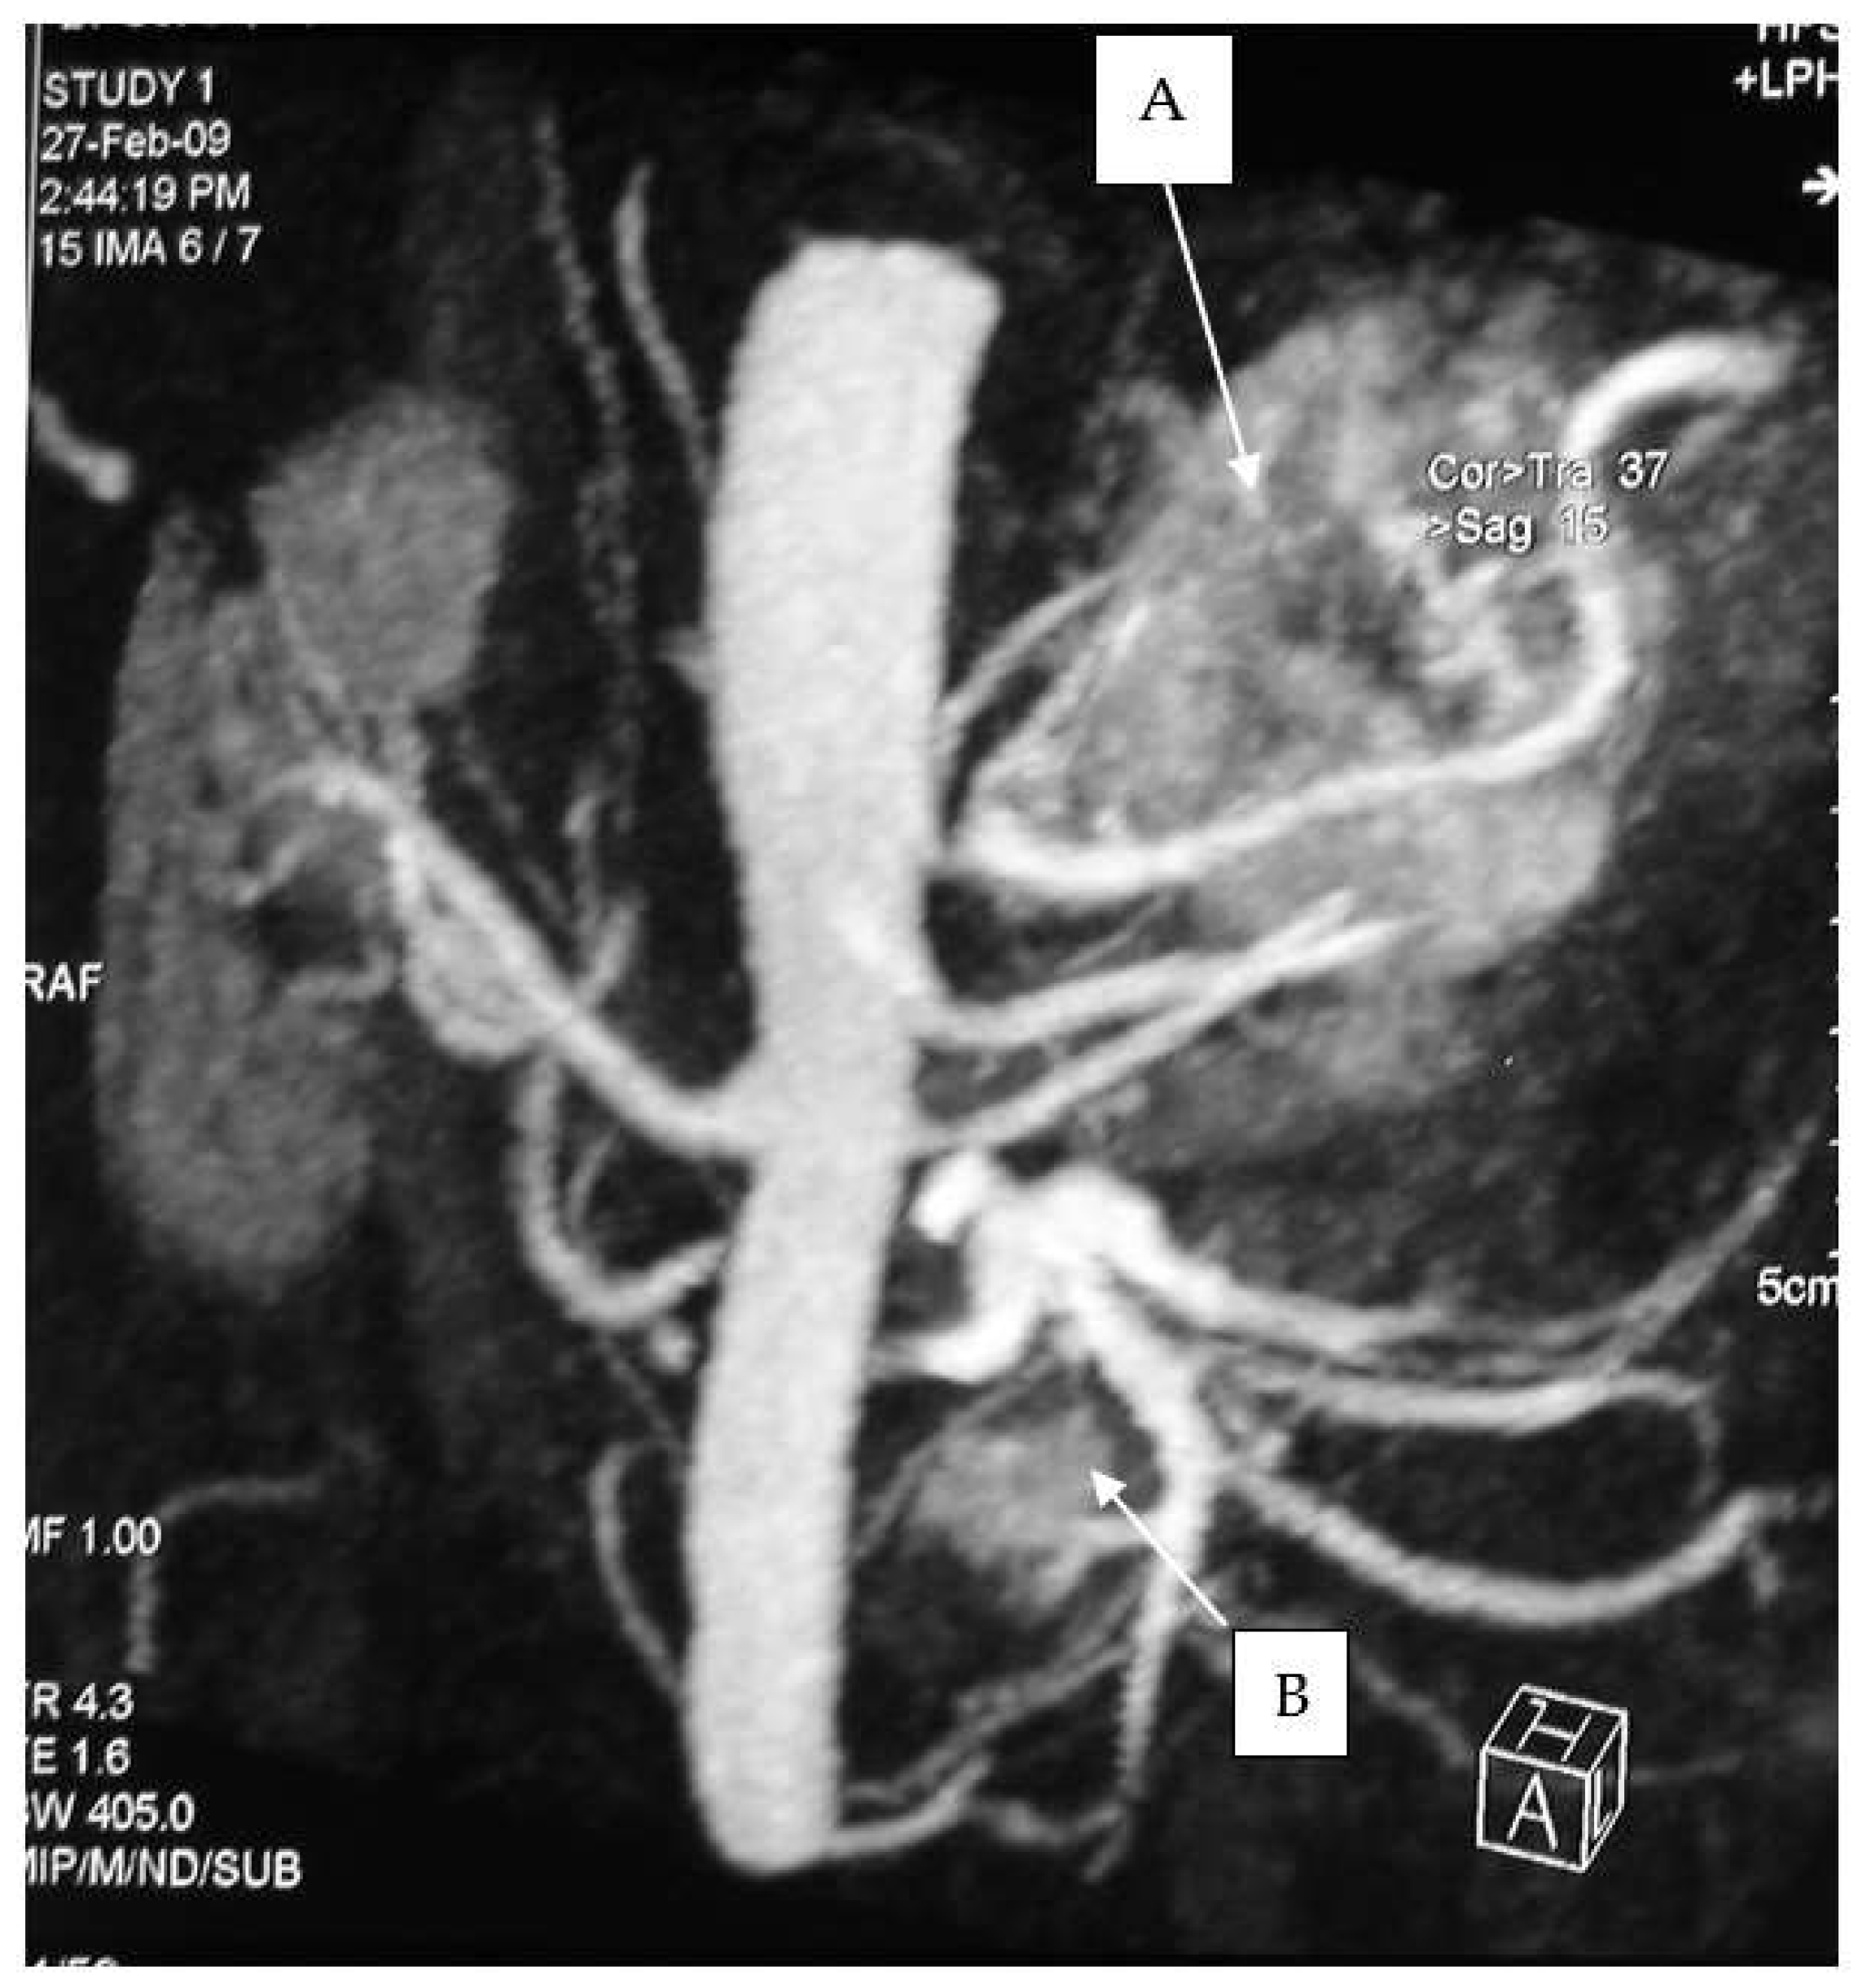

Figure 1. Adrenal pheochromocytoma (A) and abdominal paraganglioma under the left renal vein (B).

Figure 3. CT scan of an abdominal paraganglioma of above the aortic bifurcation (Zuckerkandl organ’s).